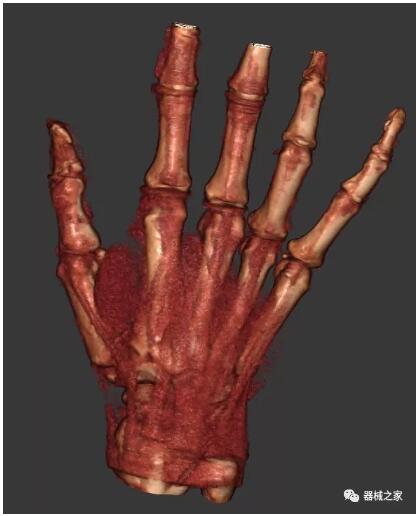

另外一款被稱為世界上最小的CT,它的重量僅300磅,不僅能夠掃查足部,還可以檢查膝蓋和上肢等。

與上面介紹的CT一樣,它同樣具有輻射低、占地空間?。?3*36)的特點,隨開隨用(支持直接接入墻上的插座)。

這款CT使用非常方便,通過上下移動保持與患者的手臂或者雙腿齊平,掃描快速,僅需要30秒左右就可以完成掃查。

以上介紹的CT均來自國外同一家公司,這些CT均配置了可視化軟件,可以進行切片、3D重建以及大型CT附帶的所有典型的操作功能。

以下是這些“特立獨行”的CT所拍出來的圖像: